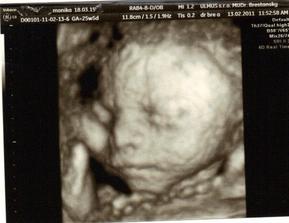

✿♥♥♥♥Bude to dievčatko!!!!! ♥♥♥♥✿

Bude to Stella 🙂

krasne 3D sono 🙂